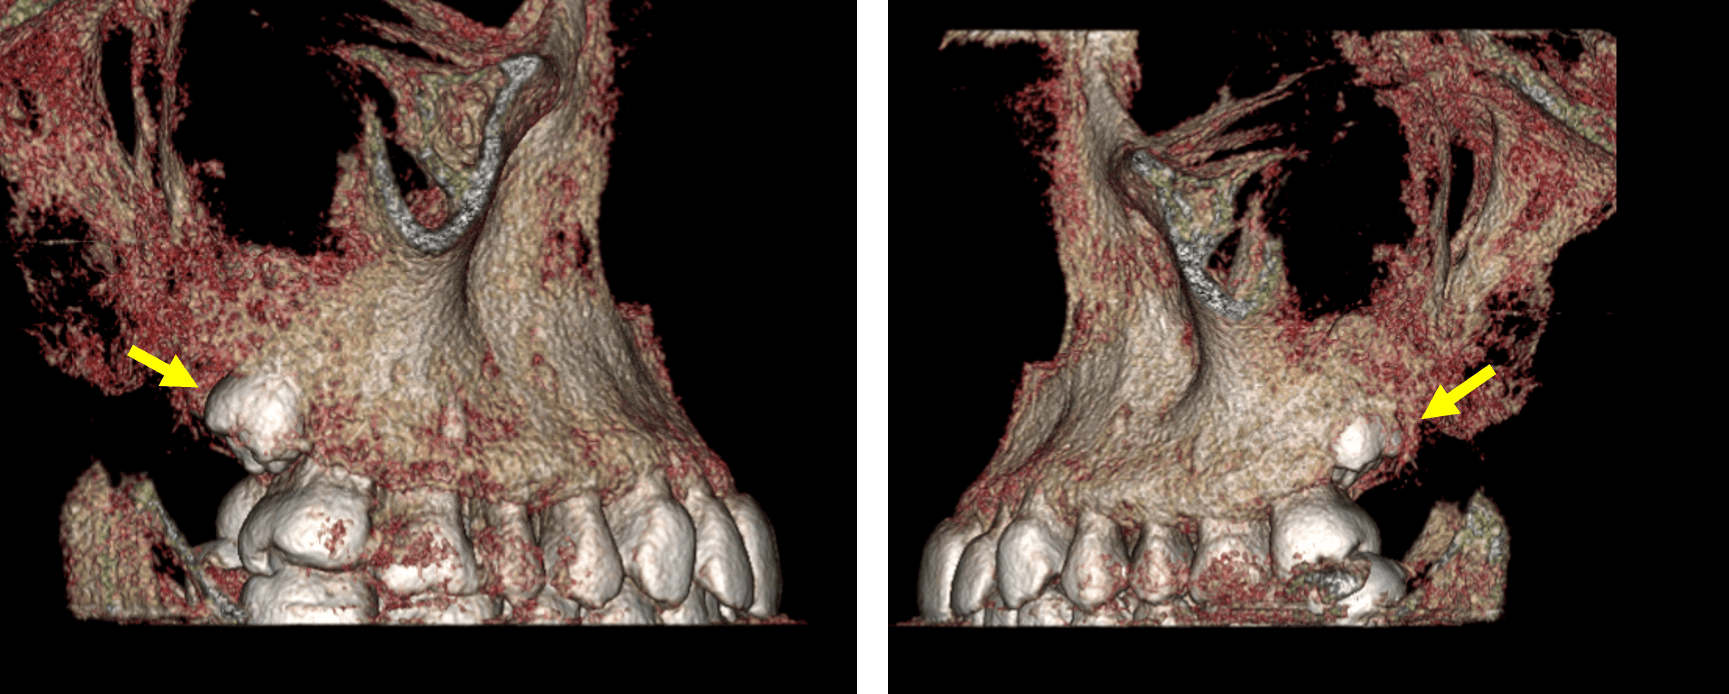

Fig.5

En la representación tridimensional (Fig.5) se observa la impactacion de los terceros molares y su inclusión parcial dentro del hueso maxilar.